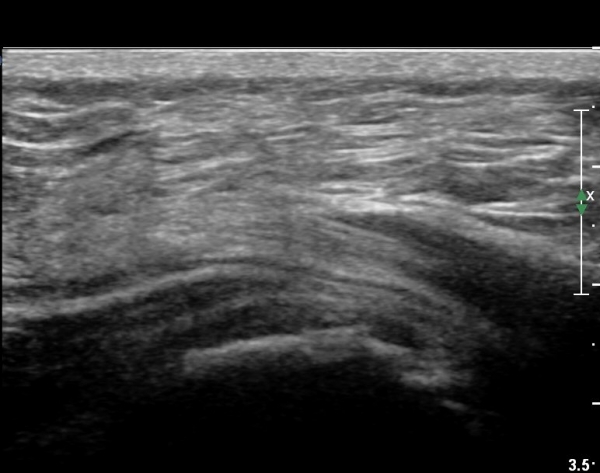

ÃÊÀ½ÆÄ °Ë»ç

Ä¡·á

Á¡¾×³¶³» ÁÖ»çÄ¡·á¿Í ¼®È¸ÀÇ ÁÖ»ç¹Ù´Ã ÀÚ±Ø(needling)